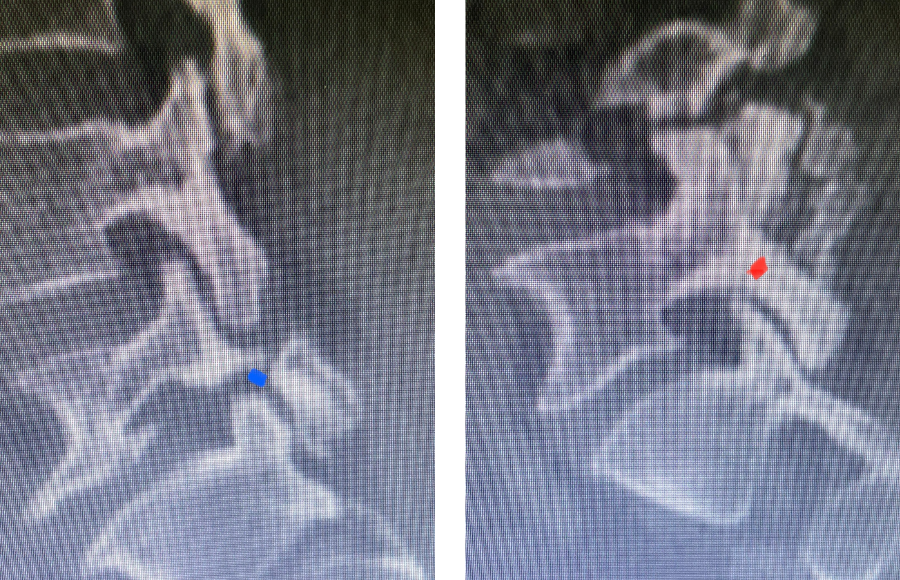

Fig 3: Sagittal CT scan with bone windows demonstrating an L5 pars defect (blue dot) and abnormal L5-S1 facet complex as well as a normal right pars structure of L5 (red dot).

Another interesting 54-year-old patient presented with low back pain and severe left lower extremity pain over two months. He had a history of falls. The pain in the leg was more bothersome to the patient. The patient had a work-up with an MRI and CT of the lumbar spine. MRI demonstrated a subtle grade 1 spondylolisthesis L5-S1 with a dysmorphic L5 vertebral body (Fig 2). There was a suggestion of a left L5 spondylolysis or defect in the bridge of bone that connects the superior facet process of the segment and the inferior facet process. A CT of the lumbar confirmed this unilateral abnormality which certainly could account for the patient’s left leg pain (Fig 3). This is an unusual finding in that most patients have bilateral pars defects. Patients with L5-S1 often have congenital abnormalities of the lumbosacral junction including weird shaped, elongated or dysplastic facet joints. A subtle L5-S1 spondylolisthesis with an associated smaller and misshapen L5 vertebral body is often associated with L5 spondylolysis. In addition, with a dysmorphic L5 vertebral body, there is secondary disc degeneration at L5-S1 and sometimes at the L4-5 disc with an associated retrolisthesis at L4-5. There is less surface to surface contact of the L4-5 and L5-S1 leading to chronic segmental instability.